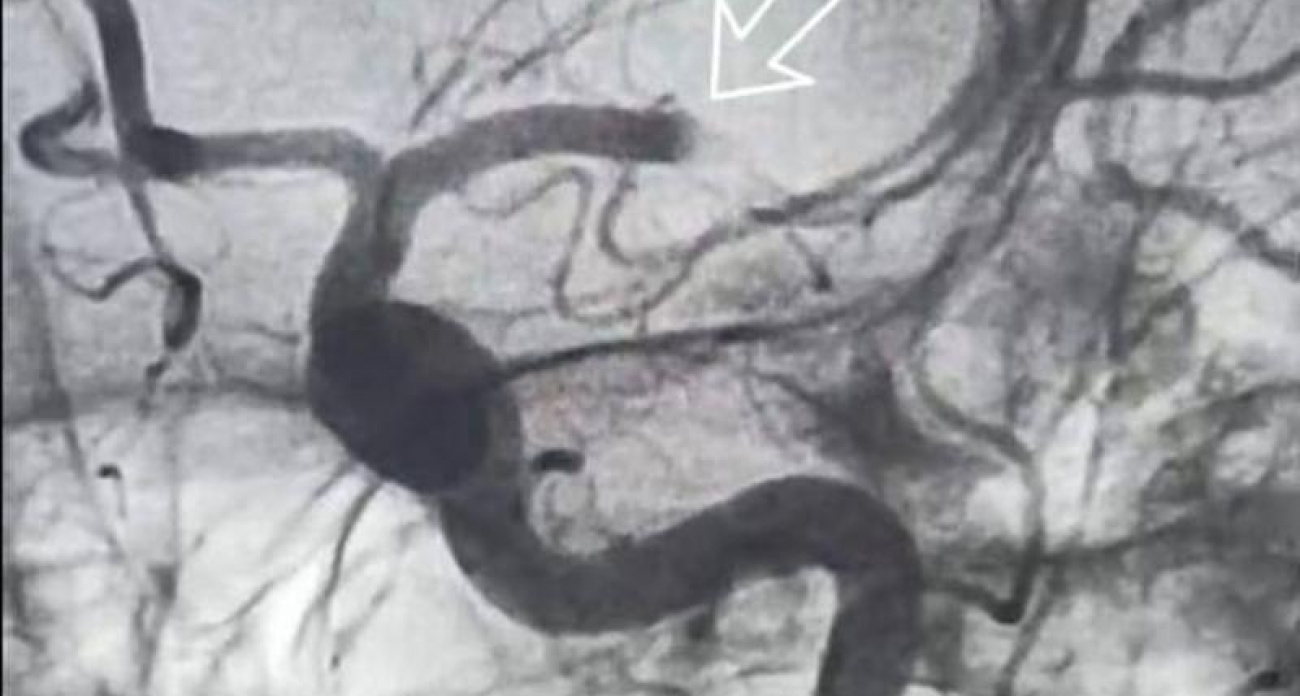

Медицинское обследование показало, что причиной инсульта стало перекрытие одного из сегментов левой среднемозговой артерии кровяным сгустком.

Врачи применили тромболитическую терапию, а затем приступили к удалению тромба. Процедура выполнялась методом однократной тромбаспирации: с помощью тонкого микрокатетера специалисты достигли места закупорки в сосуде, захватили тромб и аккуратно извлекли его.